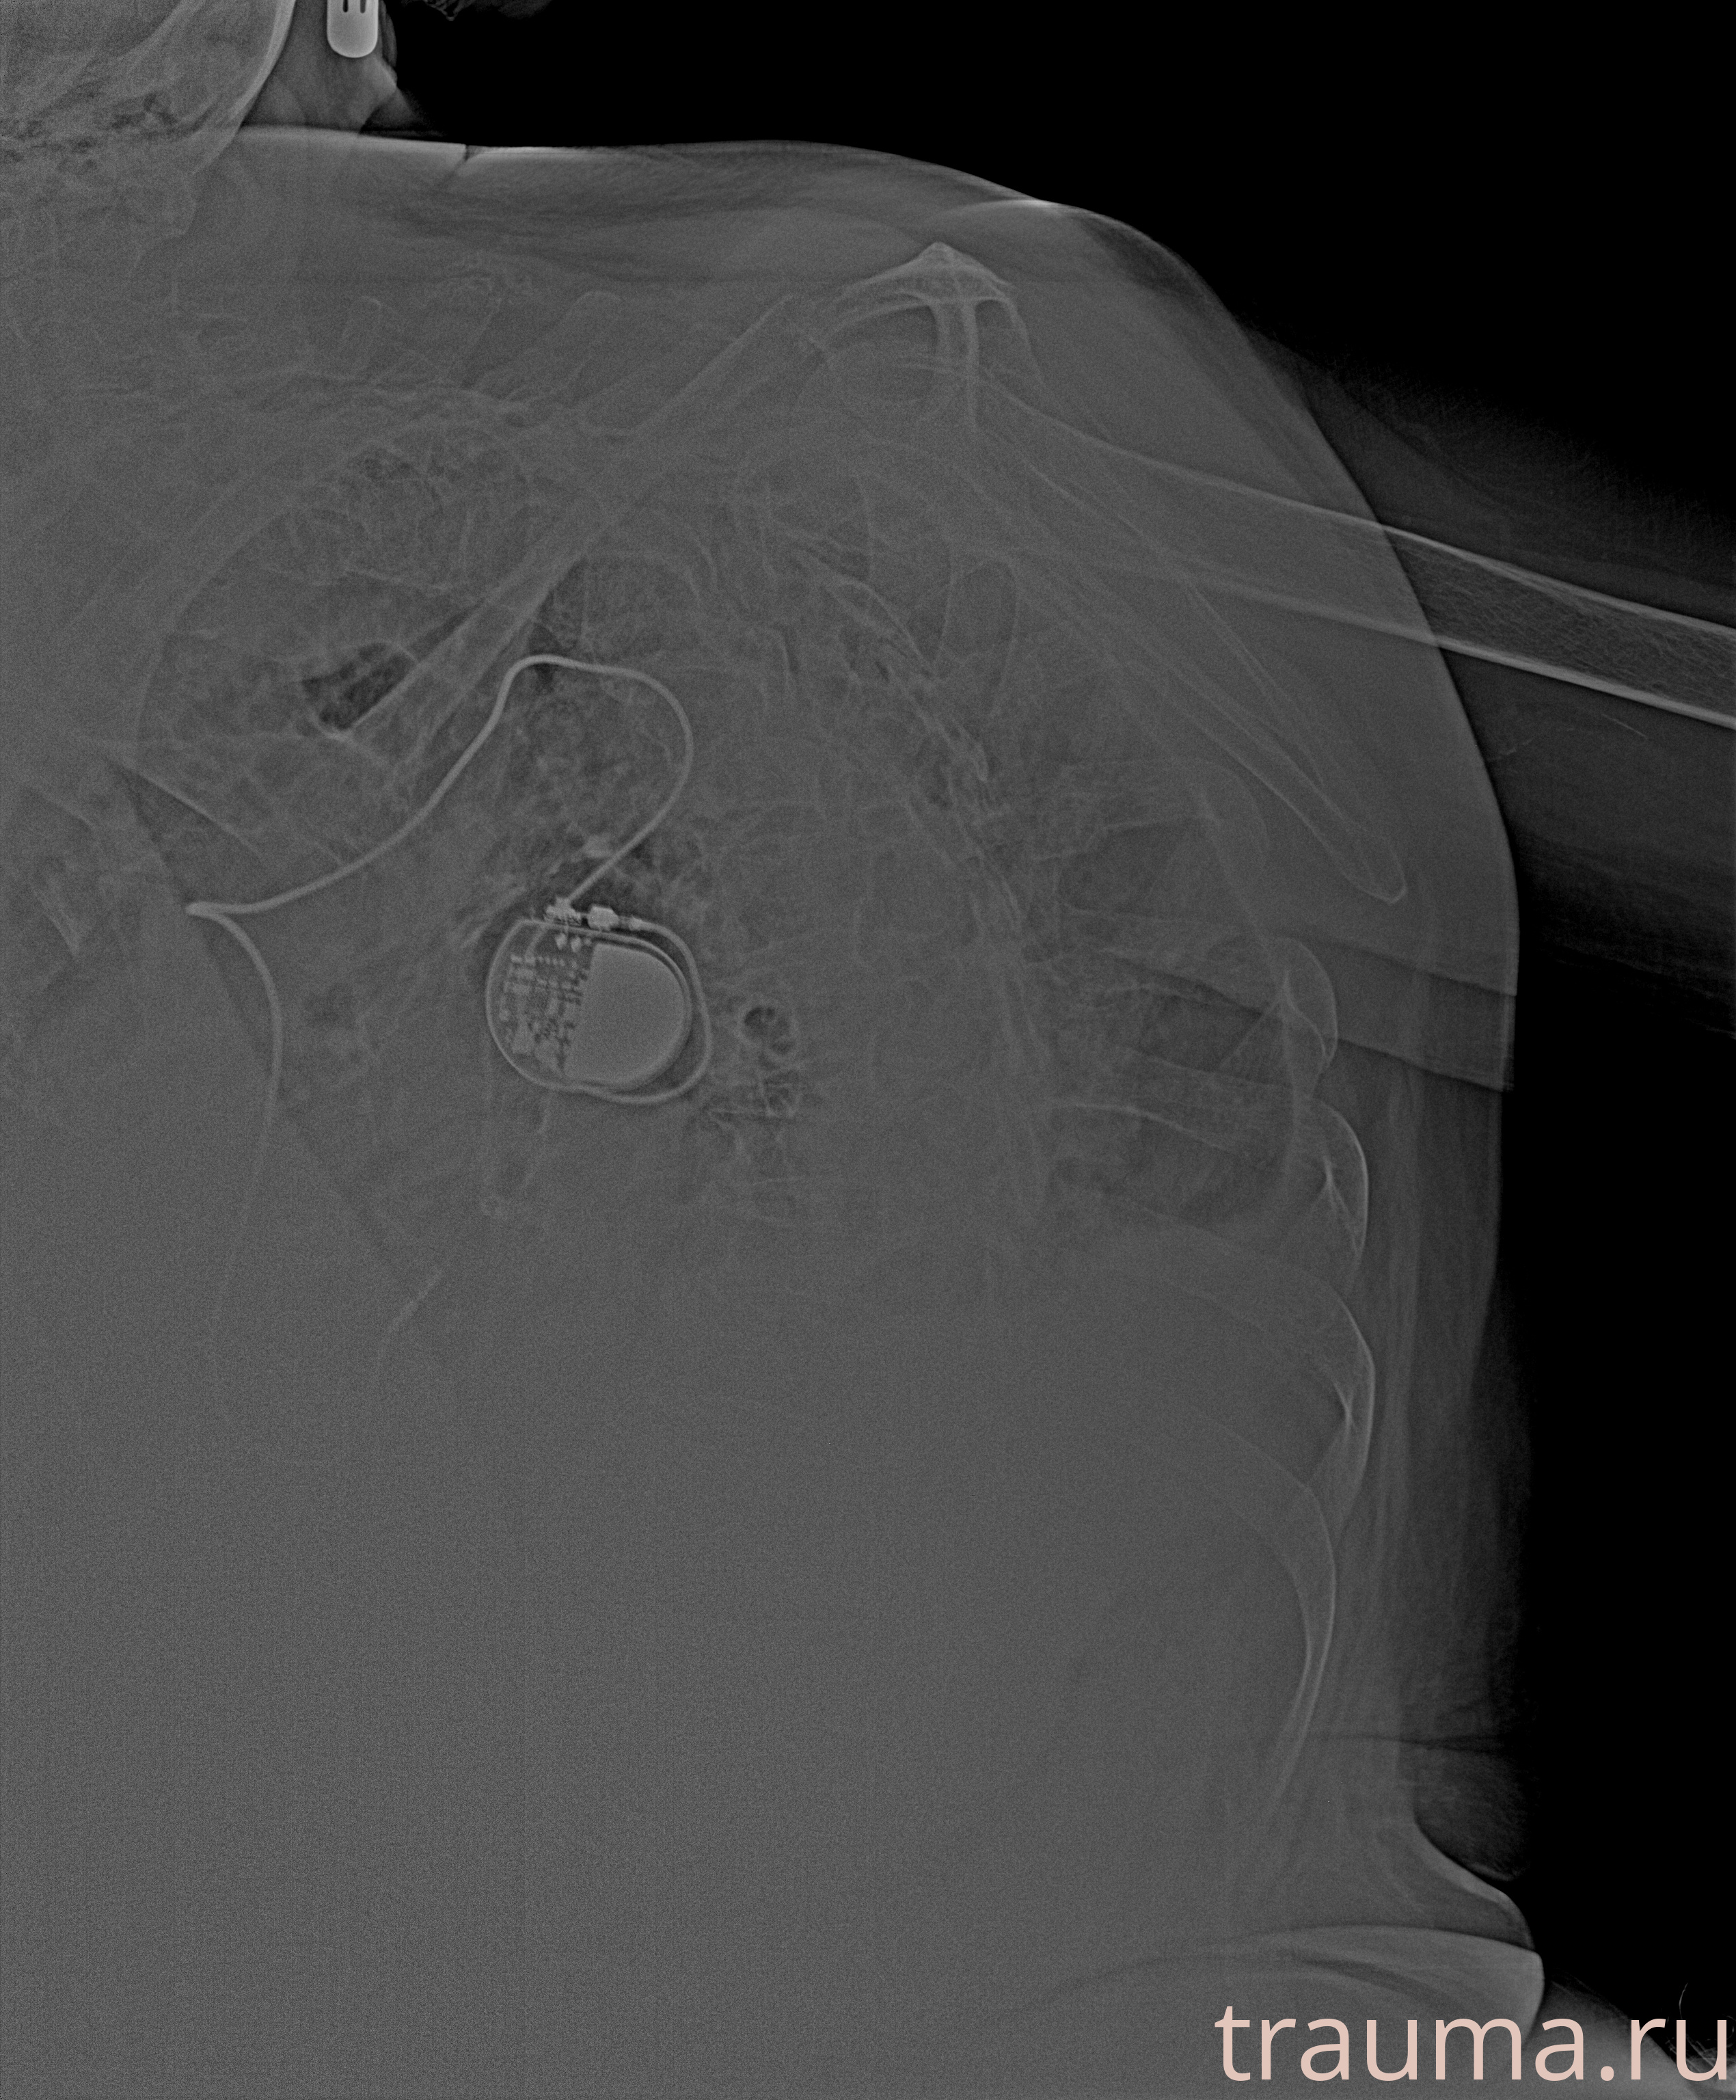

Рентгенограммы

Рентген на дому: по вашему адресу приезжает врач-рентгенолог, травматолог-ортопед с мобильным рентгеновским аппаратом, проводит диагностику травмы или заболевания, делает необходимые рентгенограммы, дает рекомендации по дальнейшему лечению. Получить качественные снимки в домашних условиях возможно благодаря уникальной методике, разработанной МосРентген Центром для института  Склифосовского

Яркость: 1   Контраст: 1   Инвертировать: 0 Увеличение: 1

Перетаскивайте мышь вверх/вниз для контраста, влево/право для яркости. Прокрутка колесом изменяет масштаб. Нажмите Сбросить для возврата к исходному изображению. При увеличении держите мышь в той области, которую хотите рассмотреть.